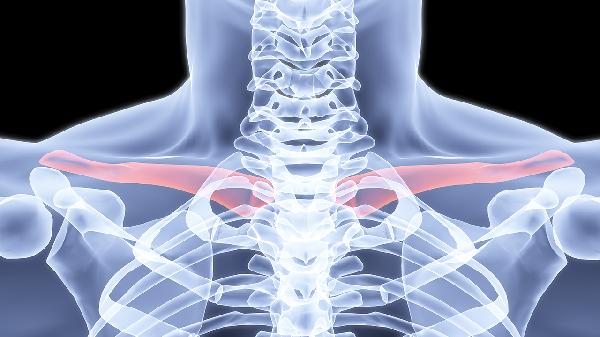

右边胸上面锁骨下面疼怎么治疗

右边胸上面锁骨下面疼可通过热敷、调整姿势、服用非甾体抗炎药、局部理疗及就医检查等方式治疗。该症状可能由肌肉拉伤、肋软骨炎、胸膜炎、颈椎病或肺部疾病等因素引起。